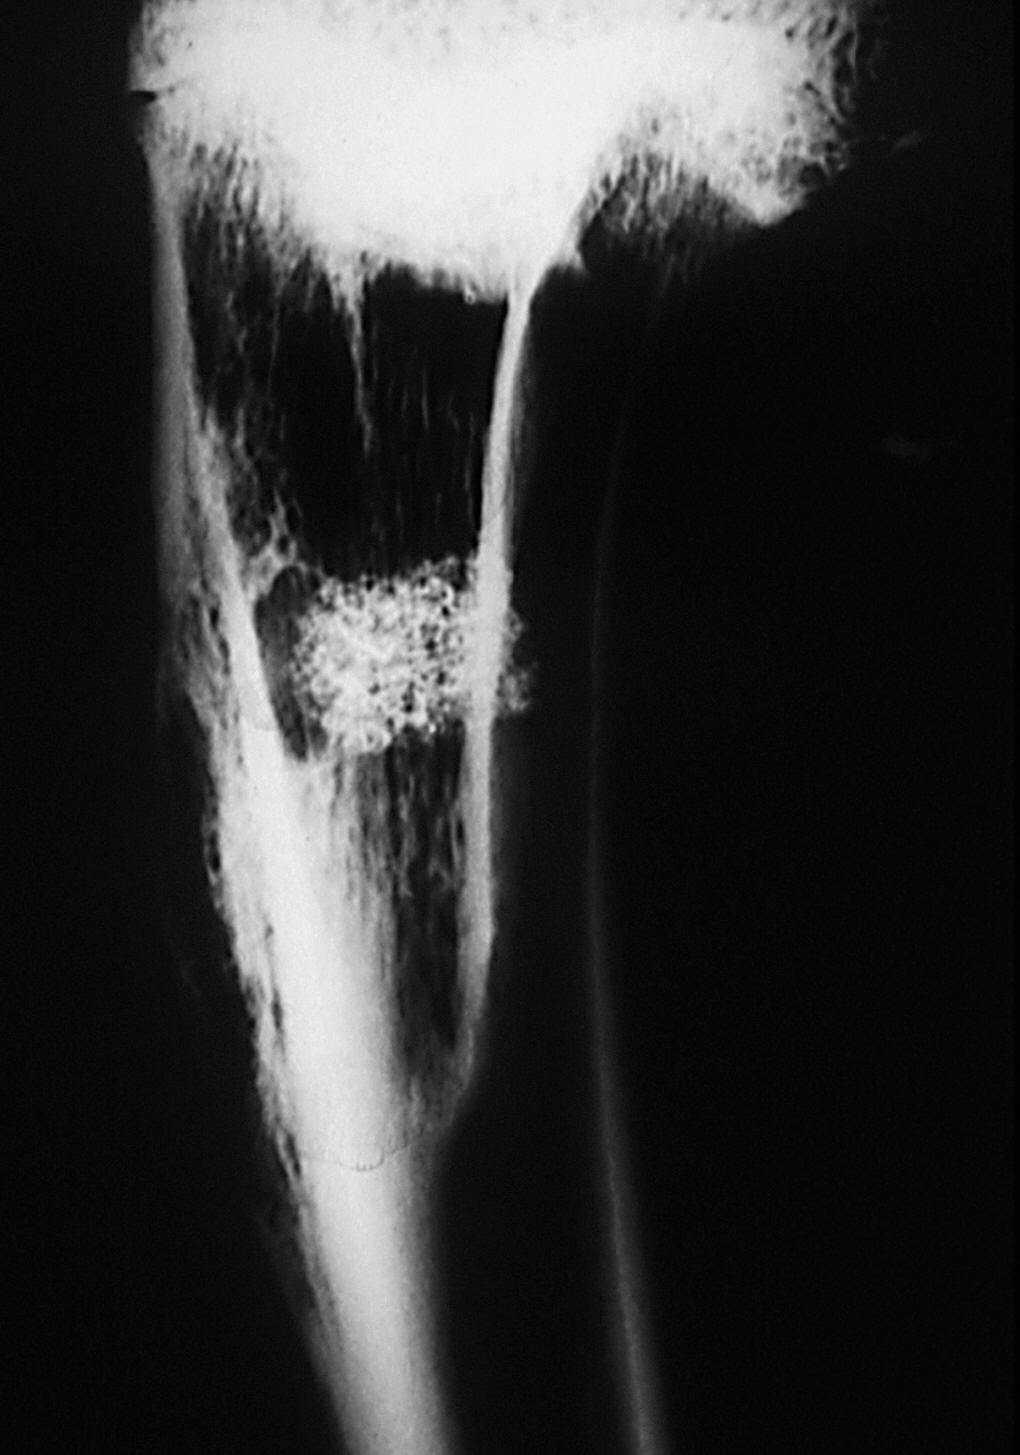

Estudio radiológico. La cortical externa presenta una densidad ósea igual a la cortical adyacente, siendo difícil reconocer el orificio de entrada. El implante junto a la cortical presentó una disminución de la densidad con respecto al grupo anterior, y una forma más ovalada con disminución de la densidad de calcio en su interior. No presenta límites radiológicamente bien definidos.

En algunas zonas existe una continuidad de la cortical con el material implantado, debido a imágenes de trabéculas óseas que parecen atravesarla. No se visualizaron límites radiográficos bien definidos (fig. 8).

Figura 8. Radiografía de tibia. Implante con disminución de tamaño y pérdida de su forma cilíndrica inicial. En algunas zonas se observan trabéculas óseas (↑) que parecen atravesar al implante (*).

Estudio morfológico. La característica distintiva de este último período del estudio fue la mayor ordenación y tamaño de las trabéculas óseas neoformadas. Asimismo, el tejido de granulación era muy escaso, menos del 10% en el implante, ya que en la periferia era sustituido por médula ósea hematopoyética de características normales. La cortical ósea estaba formada por tejido óseo compacto de características normales, que se continuaba con las trabéculas óseas que rodeaban el tejido de granulación de los poros (fig. 9).